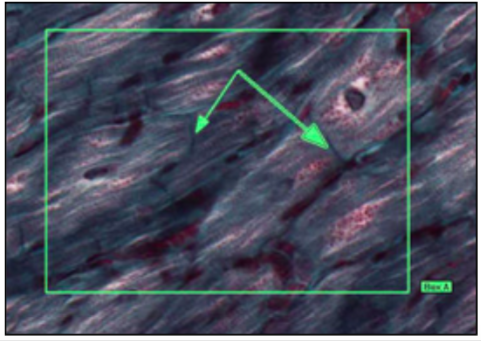

INTERCALATED DISC

- w/ desmosomes + adherent junctions (stick)

- w/ gap junctions (electrical coupling)

disc = black

myofibrial = blue/black

function:

desmosome - anchor one cardiac muscle to next by immediate cytoskeleton filaments

gap junctions - allow ion transfer between cardiac smooth muscle

electrochemical coupling - not cardiac conduction